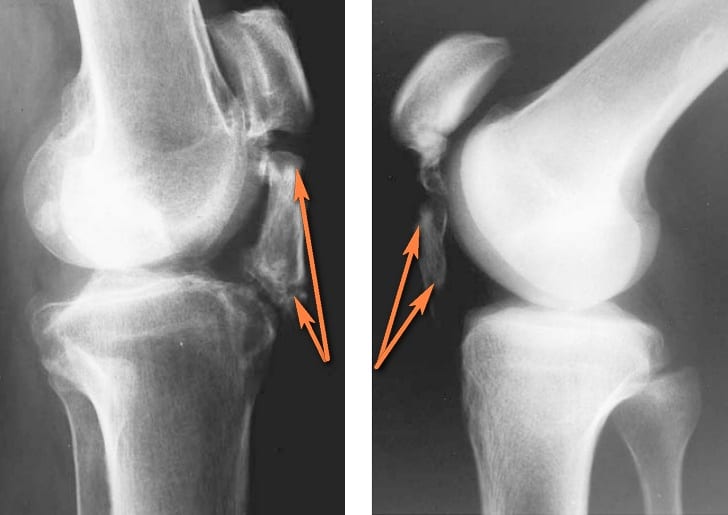

- Рентгенографии. Данный метод обследования эффективен на последних стадиях тендинита, обусловленного отложением солей или развитием бурсита.

- КТ и МРТ. Эти методы способствуют выявлению надрывов и изменений в сухожилиях.

- УЗИ. Способствует выявлению изменений структуры или сокращений сухожилий.

Своевременное и правильное диагностирование патологии способствует выявлению степени развития тендинита, а также определению конкретного поврежденного сухожилия. Помните: чем раньше вы обратитесь к специалисту, тем раньше начнется лечение и тем лучшим будет прогноз.